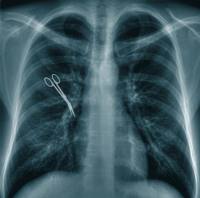

9) Caso di scuola dottrinale: garza dimenticata nello stomaco del

paziente operato di pancreatite.